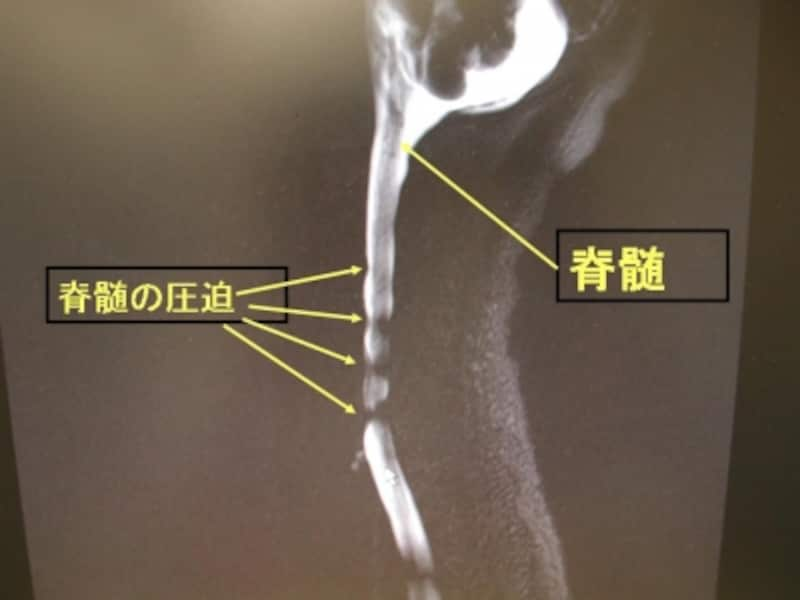

脊髄(脊柱管)の画像 4ヵ所で脊髄が狭くなっていることがわかります